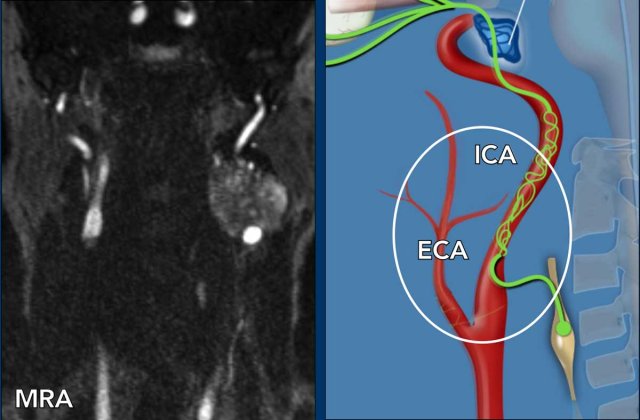

Images

The image on the right shows the typical CTA-appearance of a carotid dissection with the flame shape a couple of centimeters above the bifurcation (arrowheads).

Two weeks later and MRI was performed.

An intramural hematoma of the dissection is nicely shown (arrow).

At that time a Horner on the left was also noted and this can be explained by the pressure by the intramural hematoma of the ICA  on the post-ganglionic system (third order neuron) travelling in the adventitia of the internal and external carotid arteries to the cavernous sinus.

In these patients the Horner can resolve when the hematoma minimizes, as was the case in this patient after treatment with antiplatelet agents.

Case 5

This is a similar case.

Notice on the non enhanced CT on the left that the internal carotid is larger in diameter as a result of the hematoma.

On the enhanced CT on the right the narrowed true lumen is demonstrated (arrowhead).